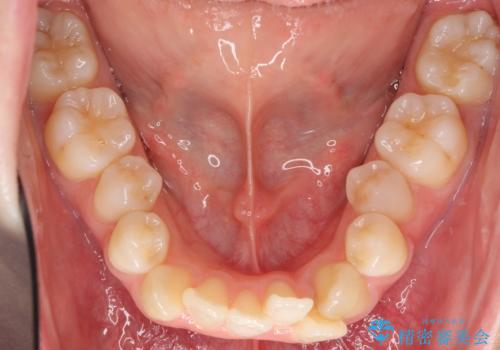

- 前歯のがたがたを主訴に来院。

八重歯と、前歯のやや開咬の症状もあり難易度としては中等度でした。

上下左右の小臼歯を抜歯し、ワイヤー矯正を行いました。